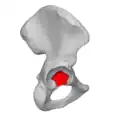

Тазовые кости в скелете таза человека выделены красным

Суставные полулунные поверхности вертлужных впадин тазовых костей участвующие в образовании тазобедренных суставов (левого и правого) отмечены красным